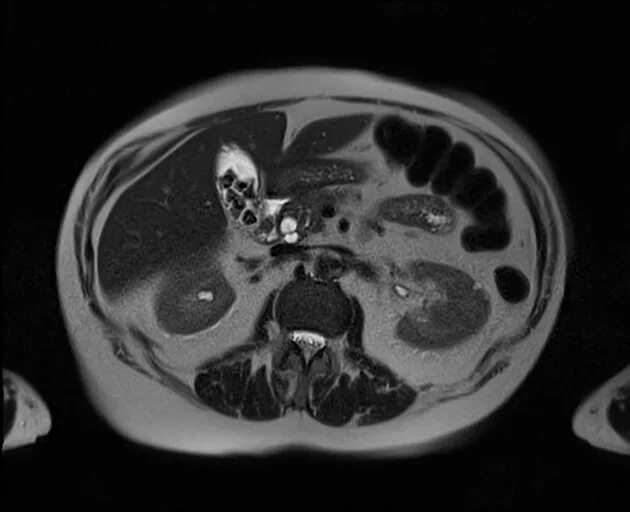

Камни в желчном мрт